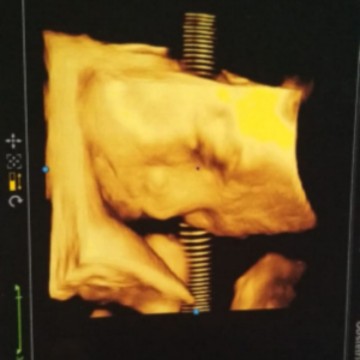

USG 4D usia 30week

aku baru aja beberapa hari lalu abis USG 4D bun. Di usia 30week . Ini kan anak pertama untuk ku . Aku jg gak ngerti di usia berapa yg bagus saat USG . Pas USG 4D di klinik lain . Sebab di tempat biasa aku cekUp katanya kalo usianya sudah 30week gak mau . Dengan Alesan susah nyarinyaa .. Bertanya lah aku di klinik tempat aku USG 4D pada dokternya yg nanganin . Alhamdulillah dokternya baik mau menjelaskan . Dan memang hampir rata rata dokter kalo sudah masuk usia 30week pd gau mau USG4D in karna posisi wajah sudah masuk katanya jd susah . Tp alhamdulillah dokter di klinik kmrn sangat baik mau dan bisa memcari dengan jelas posisi wajahnya .. Skrg tinggal ngerasai fase fase masuk 31 week yg lumayan bikin badan agak sering sakit . Tp gpp aku ikhlas . Demi Buah hati biar semua proses persalinan lancar dan Semoga Anak ku sehat sempurnah hingga tumbuh dewasa tanpa kurang satu Apapun . Amiin ❤ Yg Mau Sharing USG 4D juga boleh disini gimana kesannya dan sehappy apa liat wajah bayi kita? Semoga bermanfaat sharingnya ..